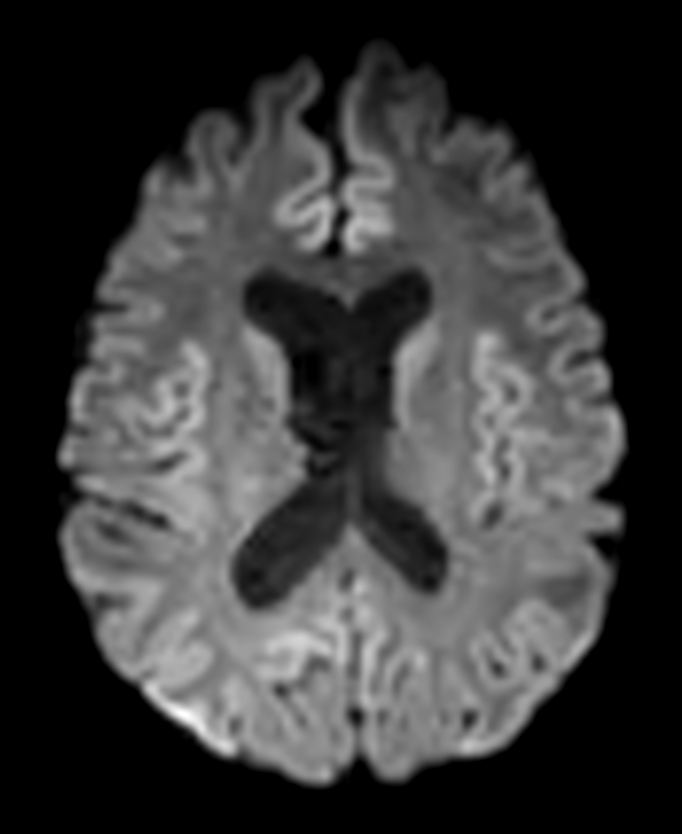

Patient with a lesion in the cerebellum. The ExamCard includes Compressed SENSE to accelerate the entire exam and techniques for motion reduced imaging (MultiVane XD), 3D imaging to acquire high resolution data in multiple directions, 3D susceptibility weighted imaging (SWIp), angiography sequences (Time-of-Flight and Contrast-Enhanced MRA with both arterial and venous phases), DTI with MultiBand SENSE to acquire a high number of diffusion directions in a short scan time and EPIC Brain to bring down any residual distortion.

DWI b1000